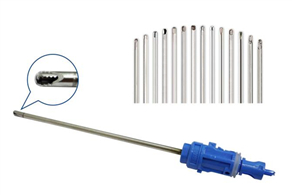

一次性使用無菌關節鏡刨刀彩頁

發布時間:2019-11-07